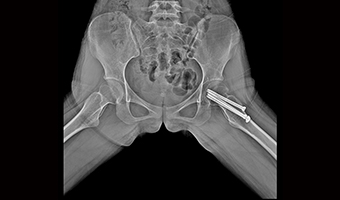

Uygulama Görüntüleri

Tam Boyut